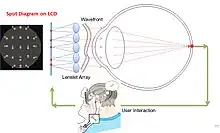

Shack–Hartmann sensors are used in astronomy to measure telescopes and in medicine to characterize eyes for corneal treatment of complex refractive errors.[9][10] Recently, Pamplona et al.[11] developed and patented[12] an inverse of the Shack–Hartmann system to measure one's eye lens aberrations. While Shack–Hartmann sensors measure the localized slope of the wavefront error using spot displacement in the sensor plane, Pamplona et al. replace the sensor plane with a high resolution visual display (e.g. a mobile phone screen) that displays spots that the user views through a lenslet array. The user then manually shifts the displayed spots (i.e. the generated wavefront) until the spots align. The magnitude of this shift provides data to estimate the first-order parameters such as radius of curvature and hence error due to defocus and spherical aberration.